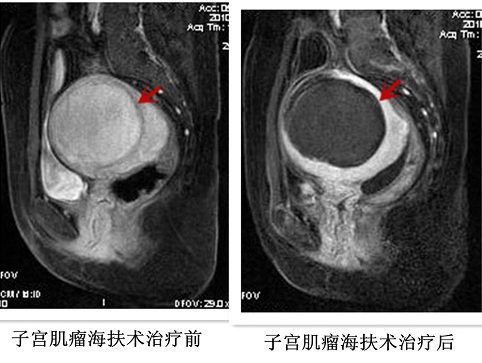

介入超声科隶属于中国人民解放军总医院(301医院)内科临床部肿瘤中心,专业于多种微创介入技术和实体肿瘤的消融治疗,是具有独立的病房和门诊的新型临床科室,开展了几乎所有热消融技术的临床应用,拥有微波消融治疗仪、射频消融治疗仪、激光消融治疗仪、JC型高强度聚焦超声肿瘤治疗系统等热消融治疗设备,以及多台高档超声仪。成功开展多种实体肿瘤的热消融治疗,主要包括:肝脏肿瘤、肾脏肾上腺肿瘤、甲状腺肿瘤、骨肿瘤、胰腺癌、乳腺肿瘤、软组织肿瘤、子宫肌瘤、子宫肌腺症以及各种腹膜后原发和转移癌等多种良性、恶性肿瘤,均取得了良好的临床疗效,积累了丰富的治疗经验,年治疗患者超过1000例次。曾获得多项国家、科技部、北京市和军队的基金资助,在国内外发表100多篇科技论文,并多次获得国家、北京市和军队科技进步奖及医疗成果奖。

高强度聚焦超声消融治疗是利用超声机械波经过精准聚焦后在很小的焦点处达到60℃-100℃的高温,非侵入性地治疗实体肿瘤的局部热消融治疗方法,使肿瘤组织达到凝固性坏死的病理变化,坏死的组织可逐渐被纤维化,体积缩小,症状缓解或甚至消失,达到治愈或姑息性治疗的目的。也可以用于放疗和化疗的热辅助治疗,能够增加肿瘤细胞对放射线和肿瘤药物的敏感性,提高临床疗效。

1.腹部的实体肿瘤(肝脏肿瘤、胰腺肿瘤、软组织肿瘤、子宫肌瘤、子宫肌腺病以及各种腹膜后原发和转移癌等);